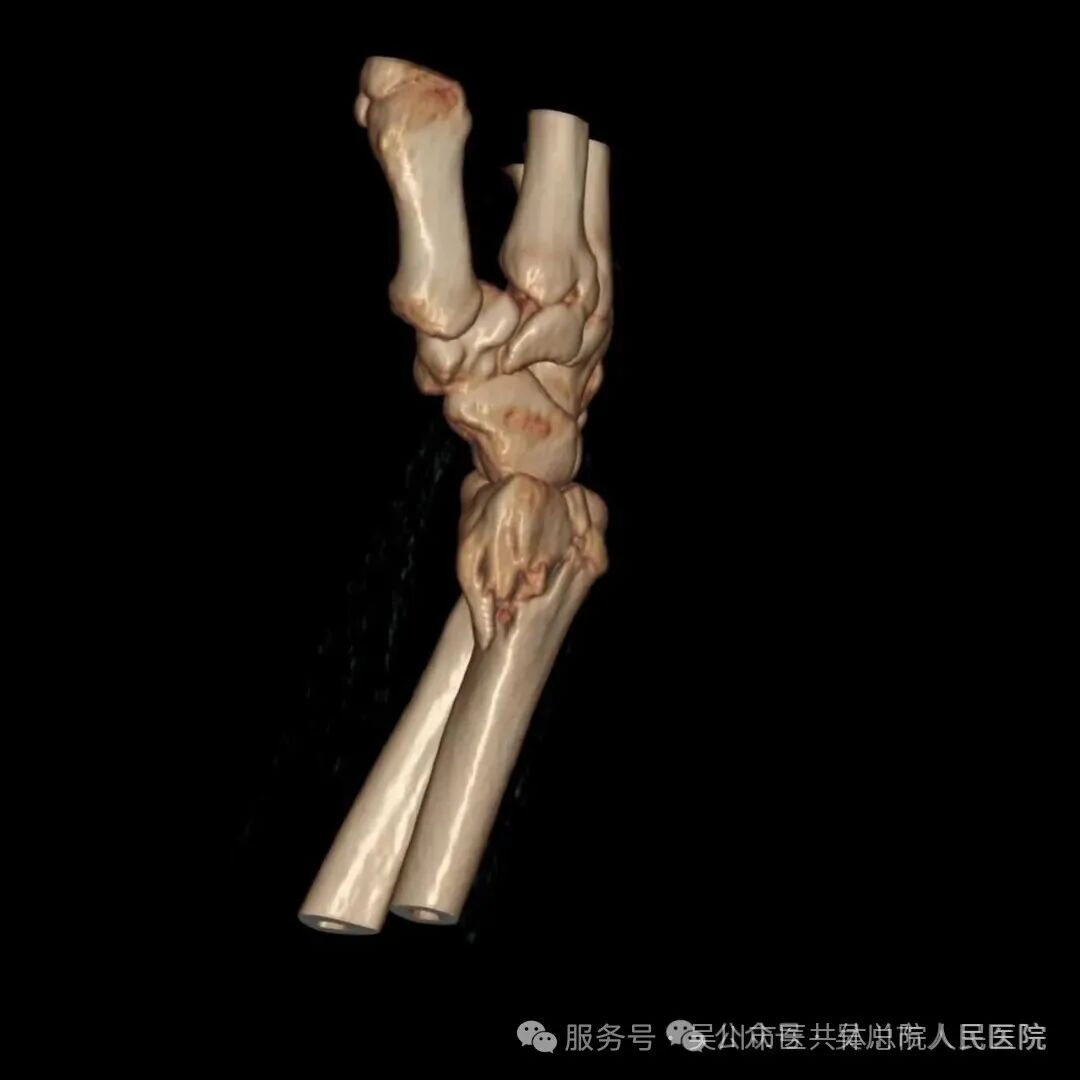

而如今,搭乘“百千万工程”优质医疗资源下沉的春风,我院骨外科已具备开展复杂骨折微创手术的能力,让潘阿姨实现了“家门口看好病”的心愿。被紧急送医后,经细致查体及影像检查,CT结果显示其右腕为粉碎性骨折,骨质碎裂,骨折线呈不规则形,关节面受到累及,若治疗不当极易引发创伤性关节炎,导致后续关节疼痛与活动受限。

结合潘阿姨的年龄与身体状况,王井旺率手术团队经过缜密讨论,决定采用微创手术治疗方案——依托“百千万工程”专项资助配备的高精度骨折复位设备,在精准定位下实现骨折端解剖复位,再用钛合金钢板进行稳固内固定。该部位骨折若处理不佳,将严重影响手腕功能。面对潘阿姨的病情与忧虑,骨一科团队快速响应,曾文晓副主任医师、欧春云副护士长、王井旺耐心向患者及家属详解病情,舒缓家属焦虑情绪。